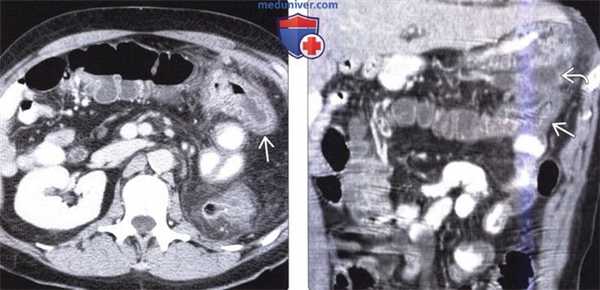

(Слева) На аксиальной КТ с контрастным усилением у мужчины 65 лет с жалобами на боль в животе визуализируется объемное образование в брыжейке с наличием кальцинатов в центре, видны также переполненные кровью брыжеечные сосуды. В правом нижнем квадранте также определяется стягивание брыжейки с деформацией кишечника.

(Справа) На КТ, полученной в венозную фазу контрастного усиления, визуализируется подозрительное объемное образование в илеоцекальной области, которое, как подтвердилось при хирургическом вмешательстве, является карциноидной опухолью. Обычно метастазы в брыжейке более очевидны на КТ по сравнению с первичной опухолью, особенно в венозную фазу контрастного усиления.